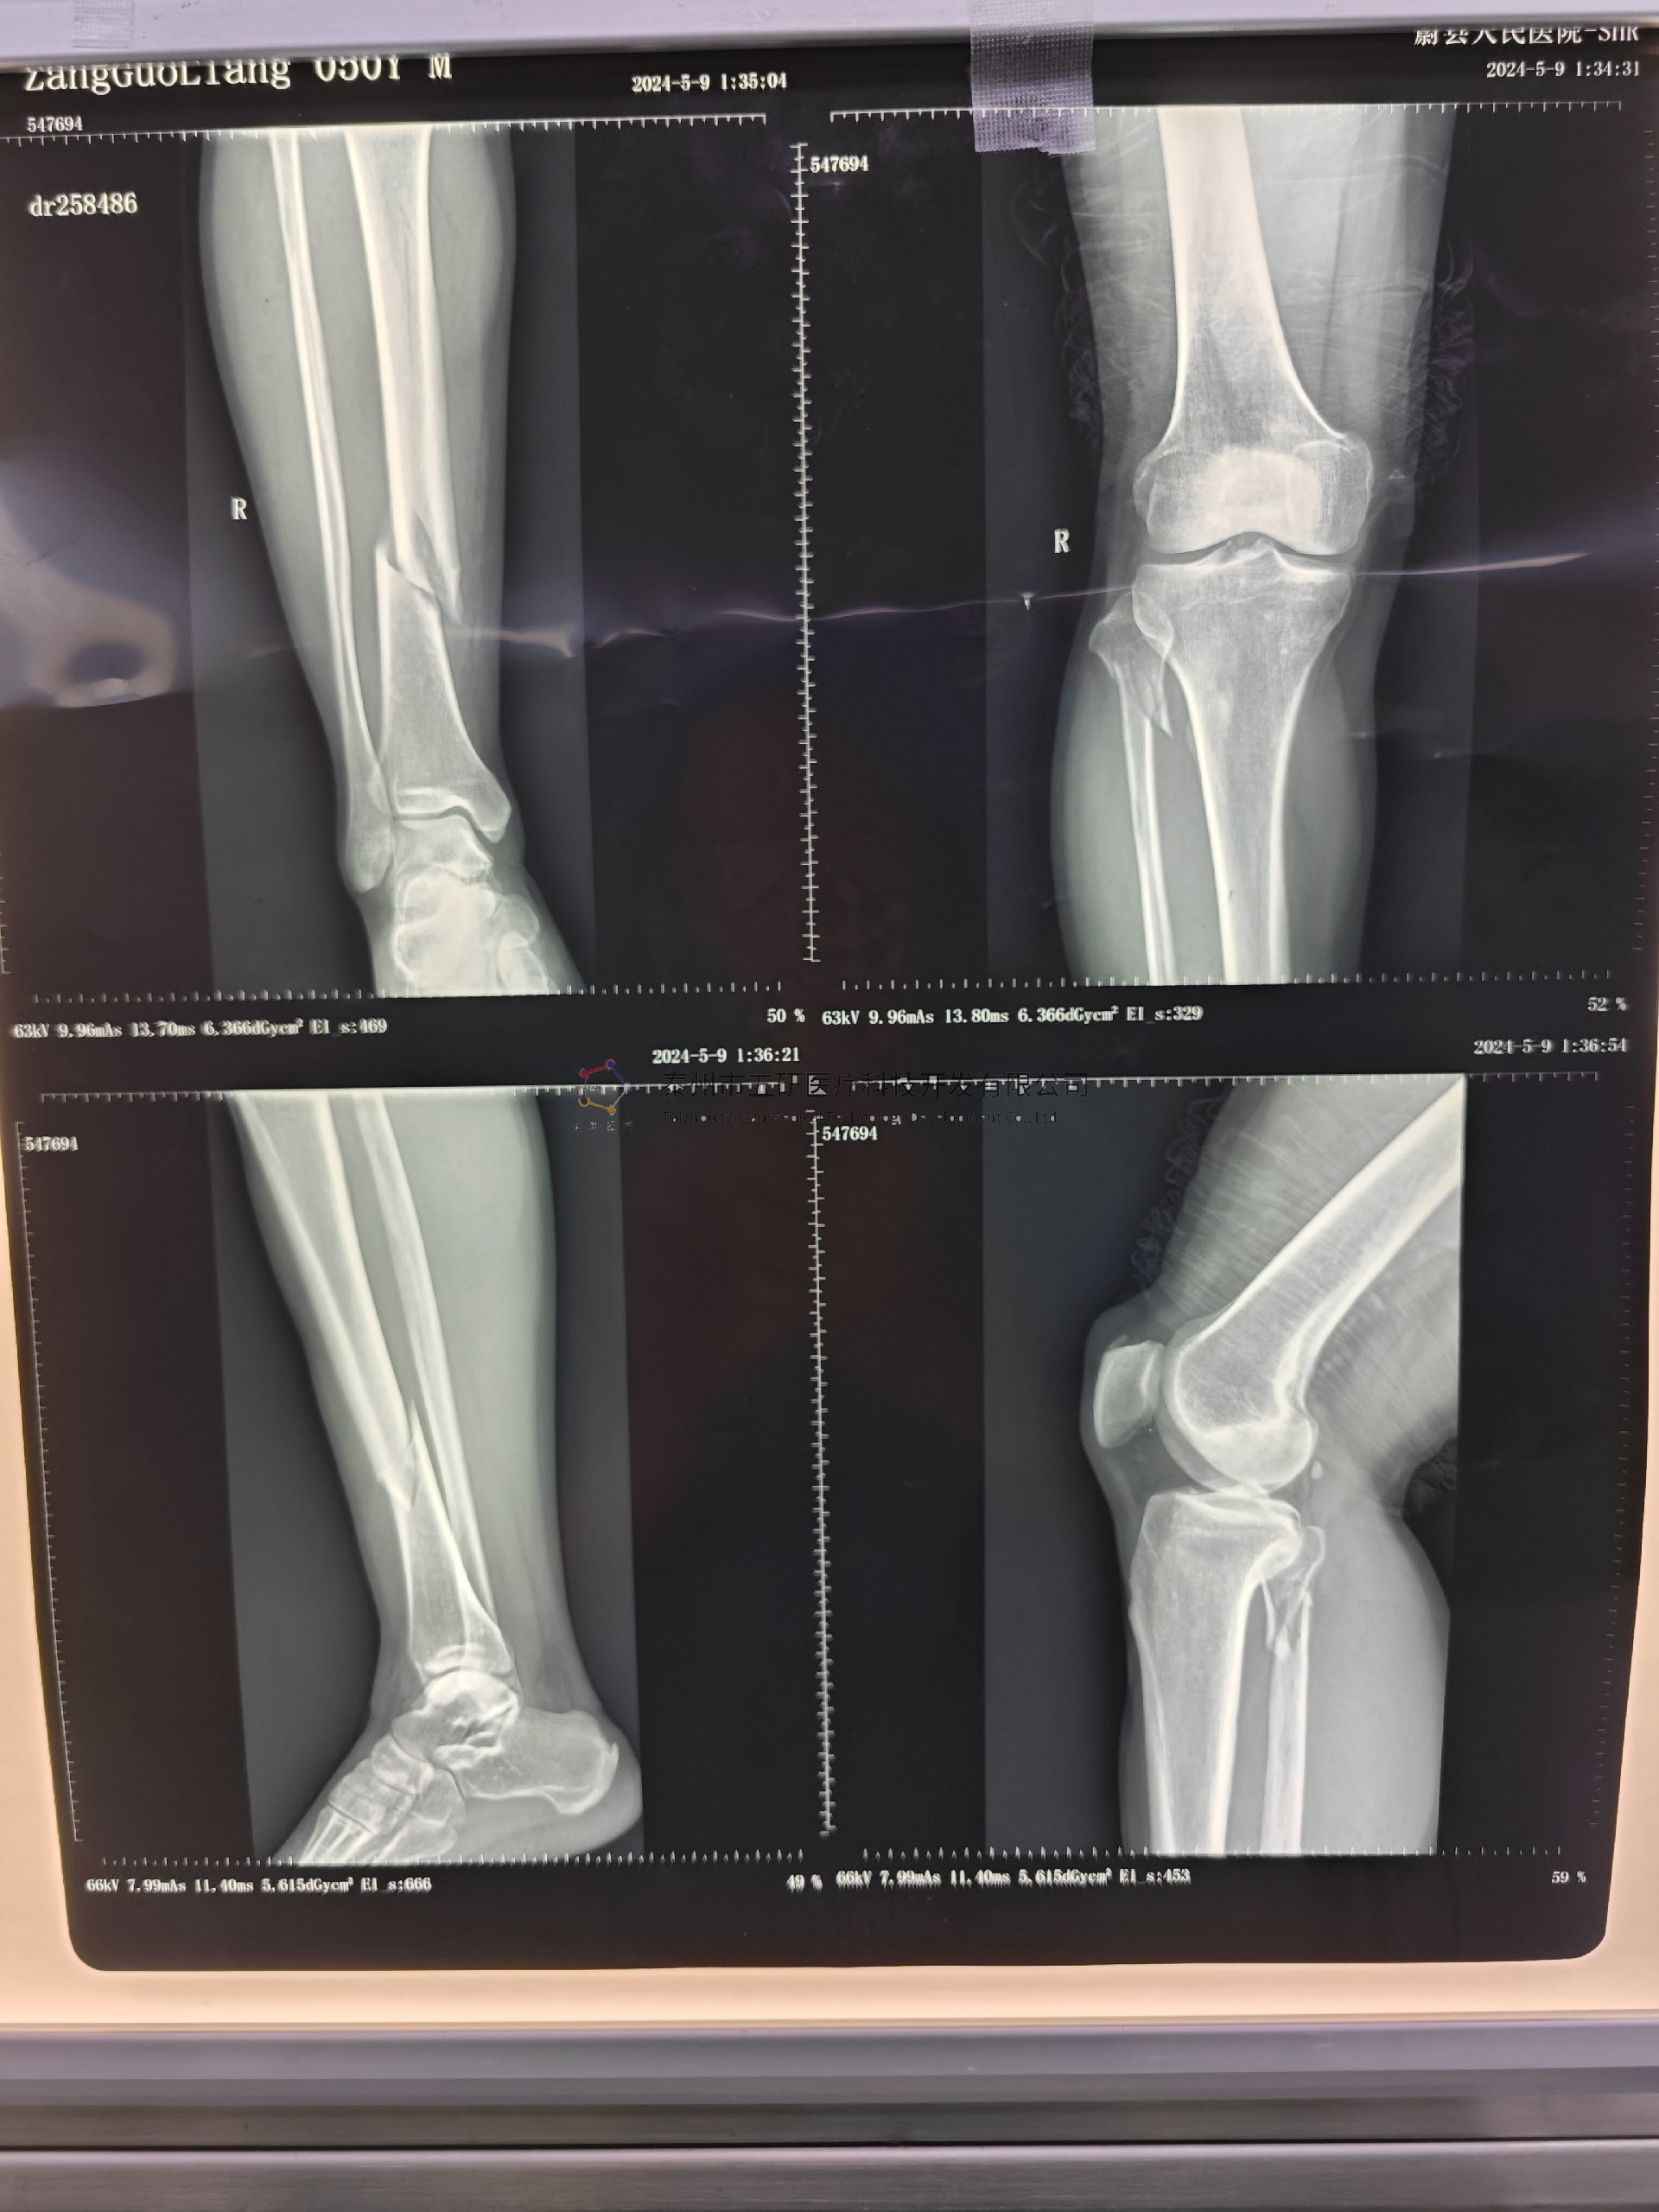

本病例由中國中醫(yī)科學(xué)院望京醫(yī)院骨骨綜科提供

術(shù)前X片